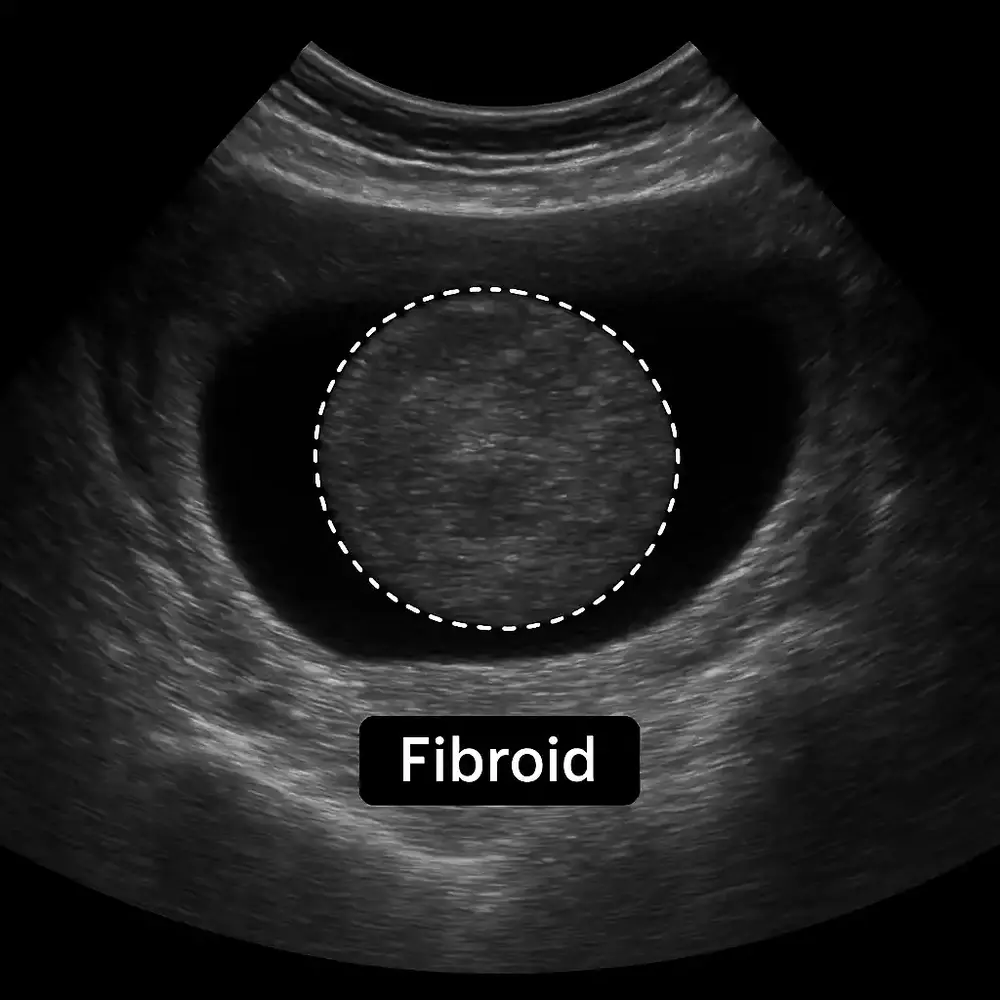

سونوگرافی رحم بهعنوان روش اصلی تشخیص